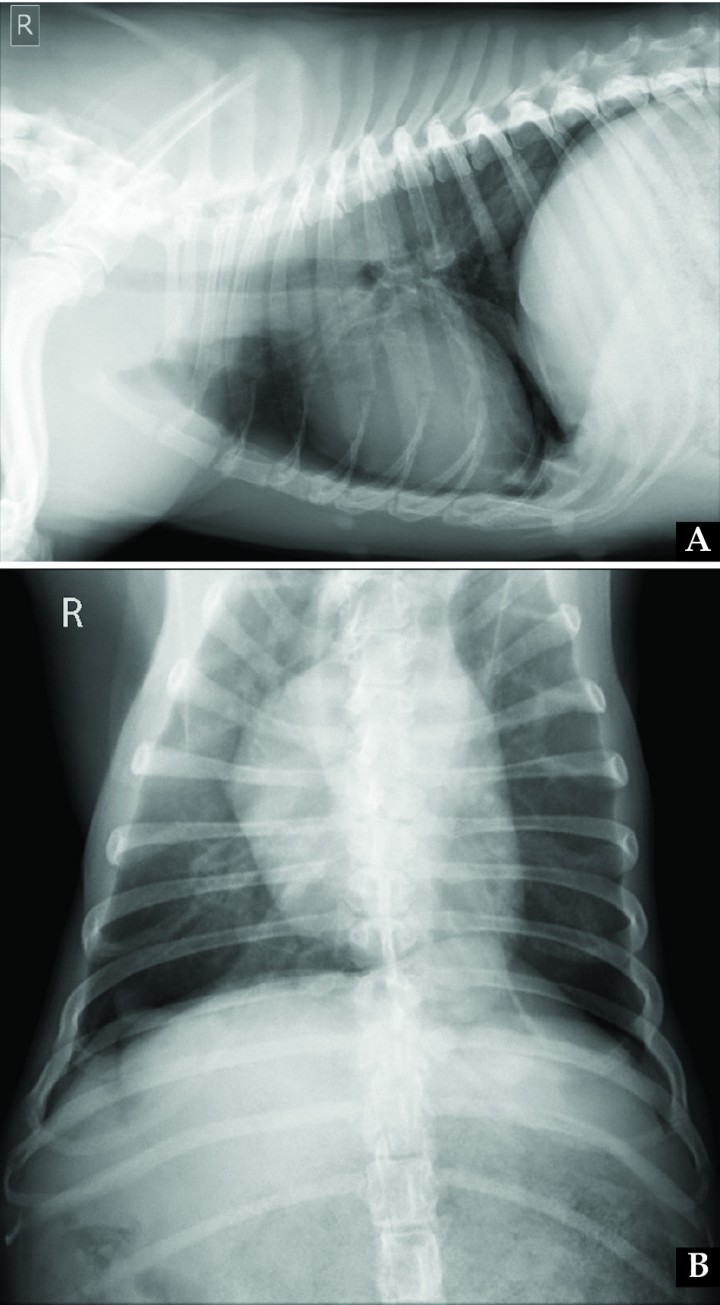

The dog recovered uneventfully from surgery, and immediately showed marked improvement of clinical signs, so that two days after was discharged from the hospital with no medical treatment. Exercise restriction and weight control were recommended. At 1-month revision, the patient presented in a good clinical condition, with a normal breathing pattern and abdominal morphology (Fig. 5), and the owner reported only mild dyspnea during exercise. Control radiographs were obtained (Fig. 6). On the dorsoventral view, normal position of the right diaphragmatic crus was observed, while on the left side cranial displacement of the left crus was present, so that partial suture loosening was suspected and close monitoring of evolution was advised. Six months after surgery the owner referred by telephone no clinical signs at rest or with mild or moderate physical activity, while strenuous exercise was still not allowed. Eighteen months after surgery, the dog was clinically normal according to the owner and referring veterinarian, and the recommended rechecks were therefore missed, also due to travel issues.

<p>(A) Right lateral and (B) dorsoventral thoracic radiographs obtained one month after surgical diaphragmatic plication. On the lateral view, diaphragm position appeared more normal when compared to Figure 2. On the dorsoventral view, normal position of the right diaphragmatic crus is observed, while on the left side cranial displacement of the left crus is present, which might be related to partial suture loosening.</p>

(A) Right lateral and (B) dorsoventral thoracic radiographs obtained one month after surgical diaphragmatic plication. On the lateral view, diaphragm position appeared more normal when compared to Figure 2. On the dorsoventral view, normal position of the right diaphragmatic crus is observed, while on the left side cranial displacement of the left crus is present, which might be related to partial suture loosening.